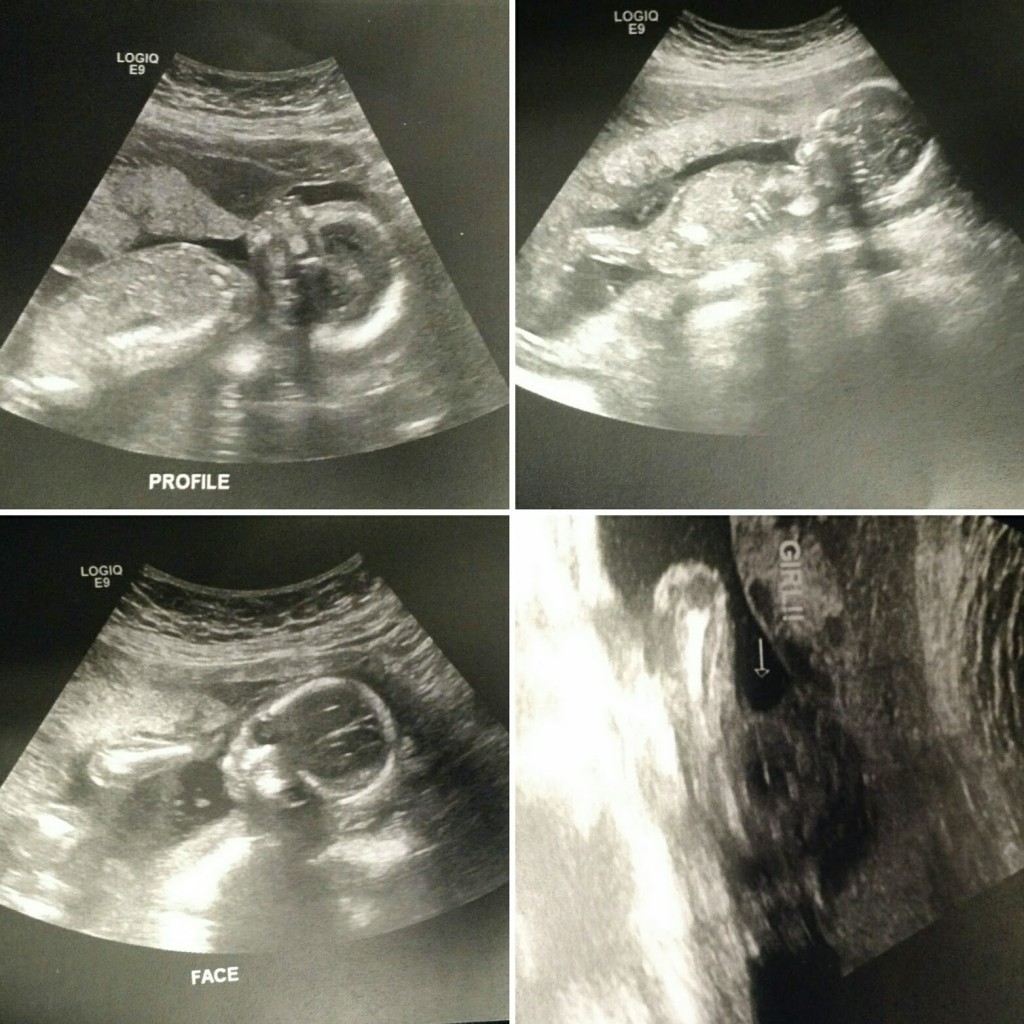

On March 31st we had our big 20 week ultrasound.

We have a healthy looking baby girl. I am still not feeling much movement yet, but the doctor says everything looks great. He did mention that my placenta in anterior which can make it more diffucult to feel movement early on. I just joke around with Brandt that after all the other kids I have nerve damage and so don’t have as much feeling anymore. LOL

Our Baby Girl is Due to Join us around August 20th!!